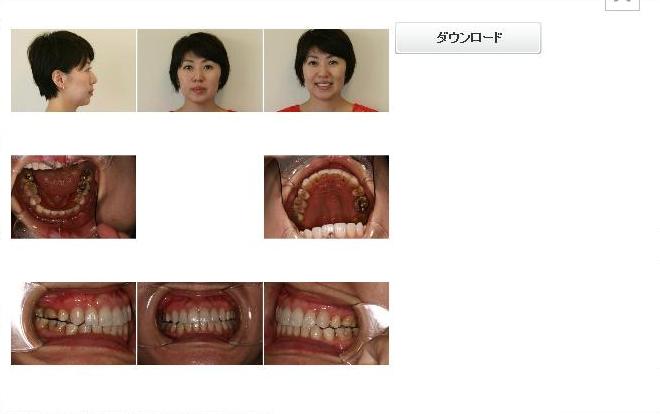

1日目(60分)・・・(虫歯・歯周病)基本検査・写真・型取り・レントゲン・セファロ分析・3Dシュミレーション→マウスピース完成

当院の治療例